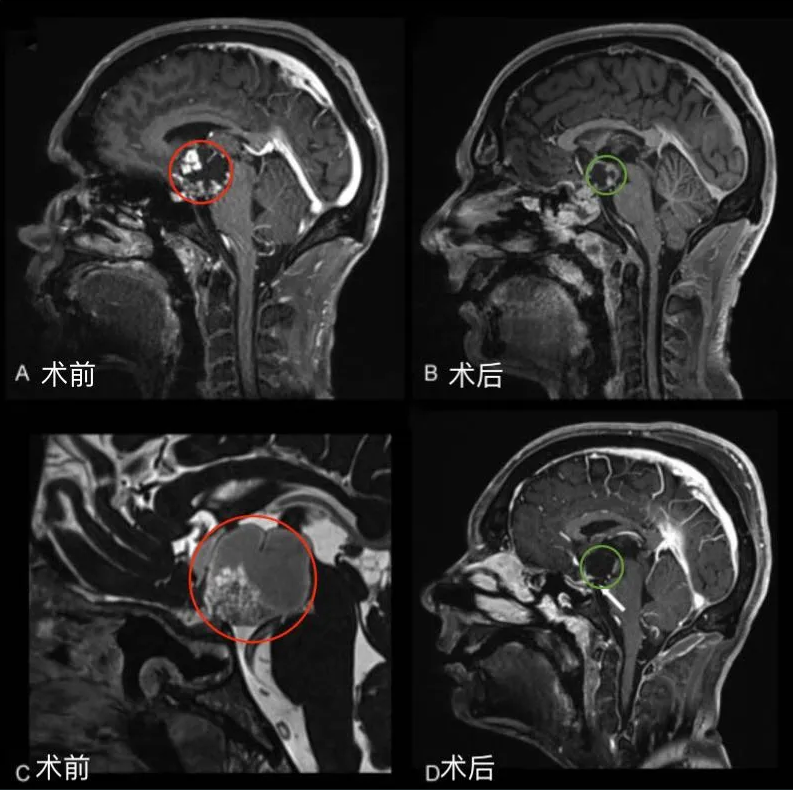

圖1后視交叉性巨大顱咽管瘤患者腫瘤術(shù)前(A,C)和術(shù)后(B,D)矢狀位增強(qiáng)MR對(duì)比,顯示腫瘤全切。